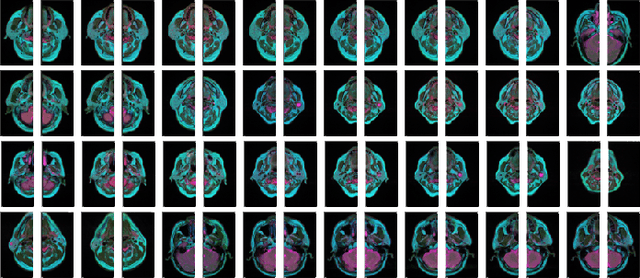

Abstract:Parotid gland tumors account for approximately 2% to 10% of head and neck tumors. Preoperative tumor localization, differential diagnosis, and subsequent selection of appropriate treatment for parotid gland tumors is critical. However, the relative rarity of these tumors and the highly dispersed tissue types have left an unmet need for a subtle differential diagnosis of such neoplastic lesions based on preoperative radiomics. Recently, deep learning methods have developed rapidly, especially Transformer beats the traditional convolutional neural network in computer vision. Many new Transformer-based networks have been proposed for computer vision tasks. In this study, multicenter multimodal parotid gland MRI images were collected. The Swin-Unet which was based on Transformer was used. MRI images of STIR, T1 and T2 modalities were combined into a three-channel data to train the network. We achieved segmentation of the region of interest for parotid gland and tumor. The DSC of the model on the test set was 88.63%, MPA was 99.31%, MIoU was 83.99%, and HD was 3.04. Then a series of comparison experiments were designed in this paper to further validate the segmentation performance of the algorithm.